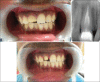

Anterior tooth fracture as a result of traumatic injuries, is frequently encountered in endodontic practice. Proper reconstruction of extensively damaged teeth can be achieved through the fragment reattachment procedure known as "biological restoration." This case report refers to the esthetics and functional recovery of extensively damaged maxillary central incisor through the preparation and adhesive cementation of "biological post" in a young patient. Biological post obtained through extracted teeth from another individual-represent a low-cost option and alternative technique for the morphofunctional recovery of extensively damaged anterior teeth.